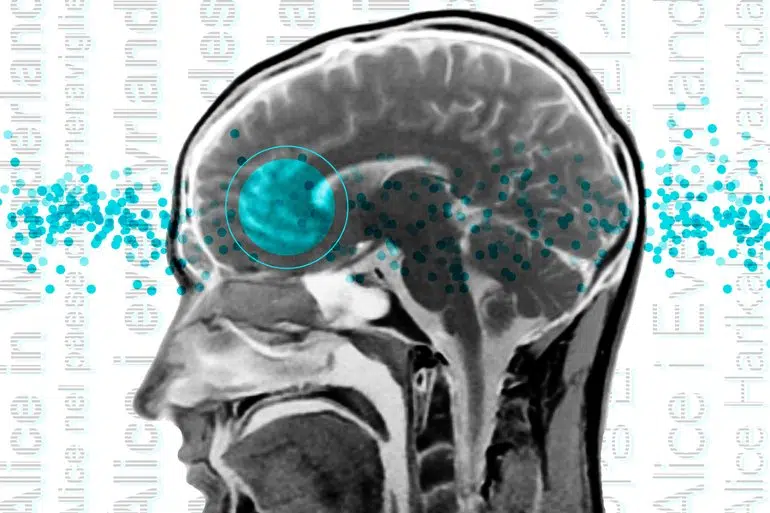

Over several decades, neuroscientists have created a well-defined map of the brain’s “language network,” or the regions of the brain that are specialized for processing language. Found primarily in the left hemisphere, this network includes regions within Broca’s area, as well as in other parts of the frontal and temporal lobes.

The precise locations and shapes of language areas differ across individuals, so to find the language network, researchers ask each person to perform a language task while scanning their brains with functional magnetic resonance imaging (fMRI). Listening to or reading sentences in one’s native language should activate the language network.

For the new study, the researchers performed brain imaging of two speakers of 45 different languages, representing 12 different language families. Their goal was to see if key properties of the language network, such as location, left lateralization, and selectivity, were the same in those participants as in people whose native language is English.

The team found that the language networks of participants in this study were found in approximately the same brain regions, and had the same selectivity, as those of native speakers of English.